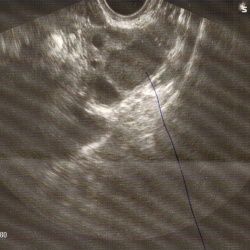

Пожилая женщина пришла на обследование. Жалоб нет. Решила просто провериться. В правой почке обнаружил вот такую картину. Считаю, что это многокамерная киста почечного синуса. Со слов пациентки...